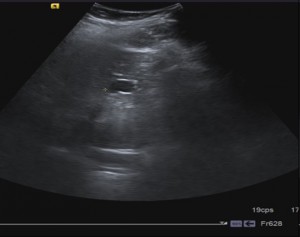

Puede observarse en la imagen un hígado de tamaño y ecogenicidad normales y la presencia de una LOE (Lesión Ocupante de Espacio) redondeada en relación con un quiste de 2 cm, que se corresponde con la lesión hipodensa descrita en el estudio del TAC.